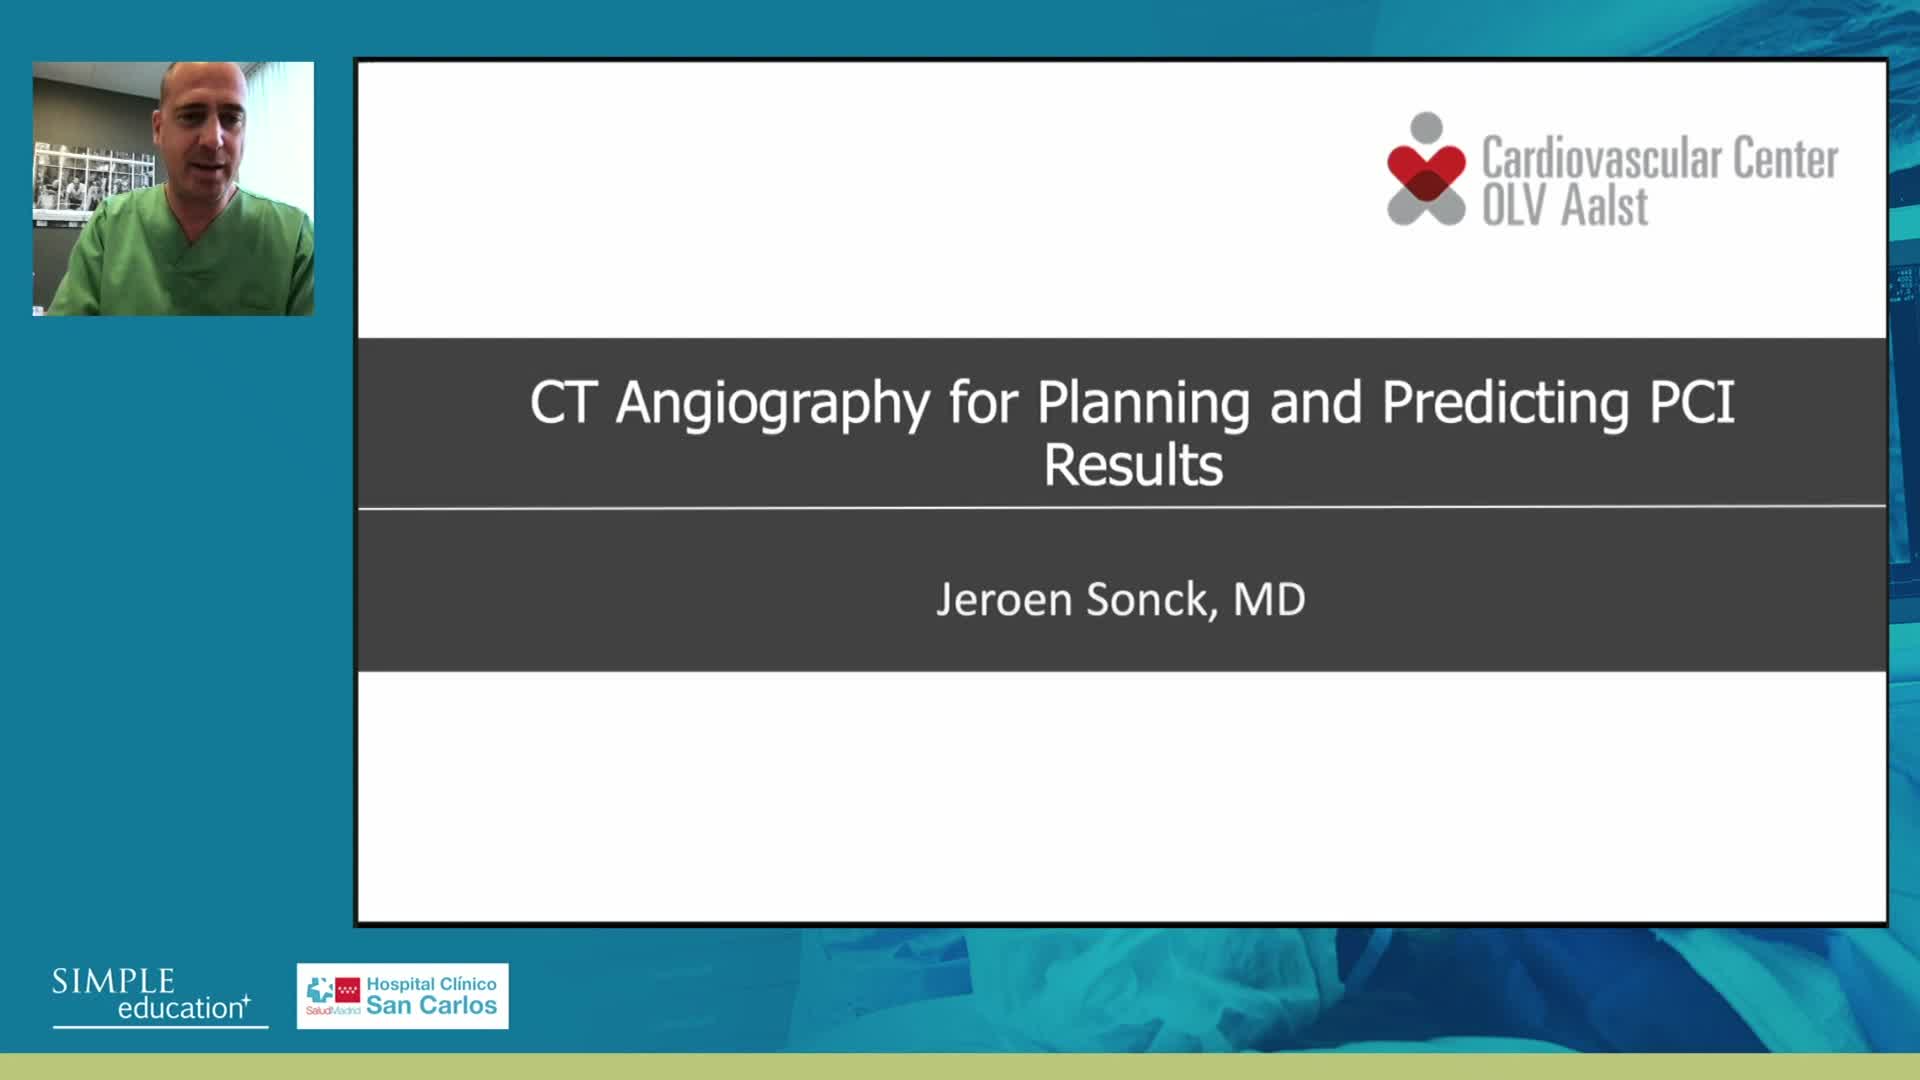

Advances in Co-registration, Coronary Physiology & Intra Coronary Imaging - April 2024 Day One

Advances in Co-registration, Coronary Physiology & Intra Coronary Imaging - April 2024 Day Two

Advances in Co-registration, Coronary Physiology & Intra Coronary Imaging - November 2023 Day One

Advances in Co-registration, Coronary Physiology & Intra Coronary Imaging - November 2023 Day Two